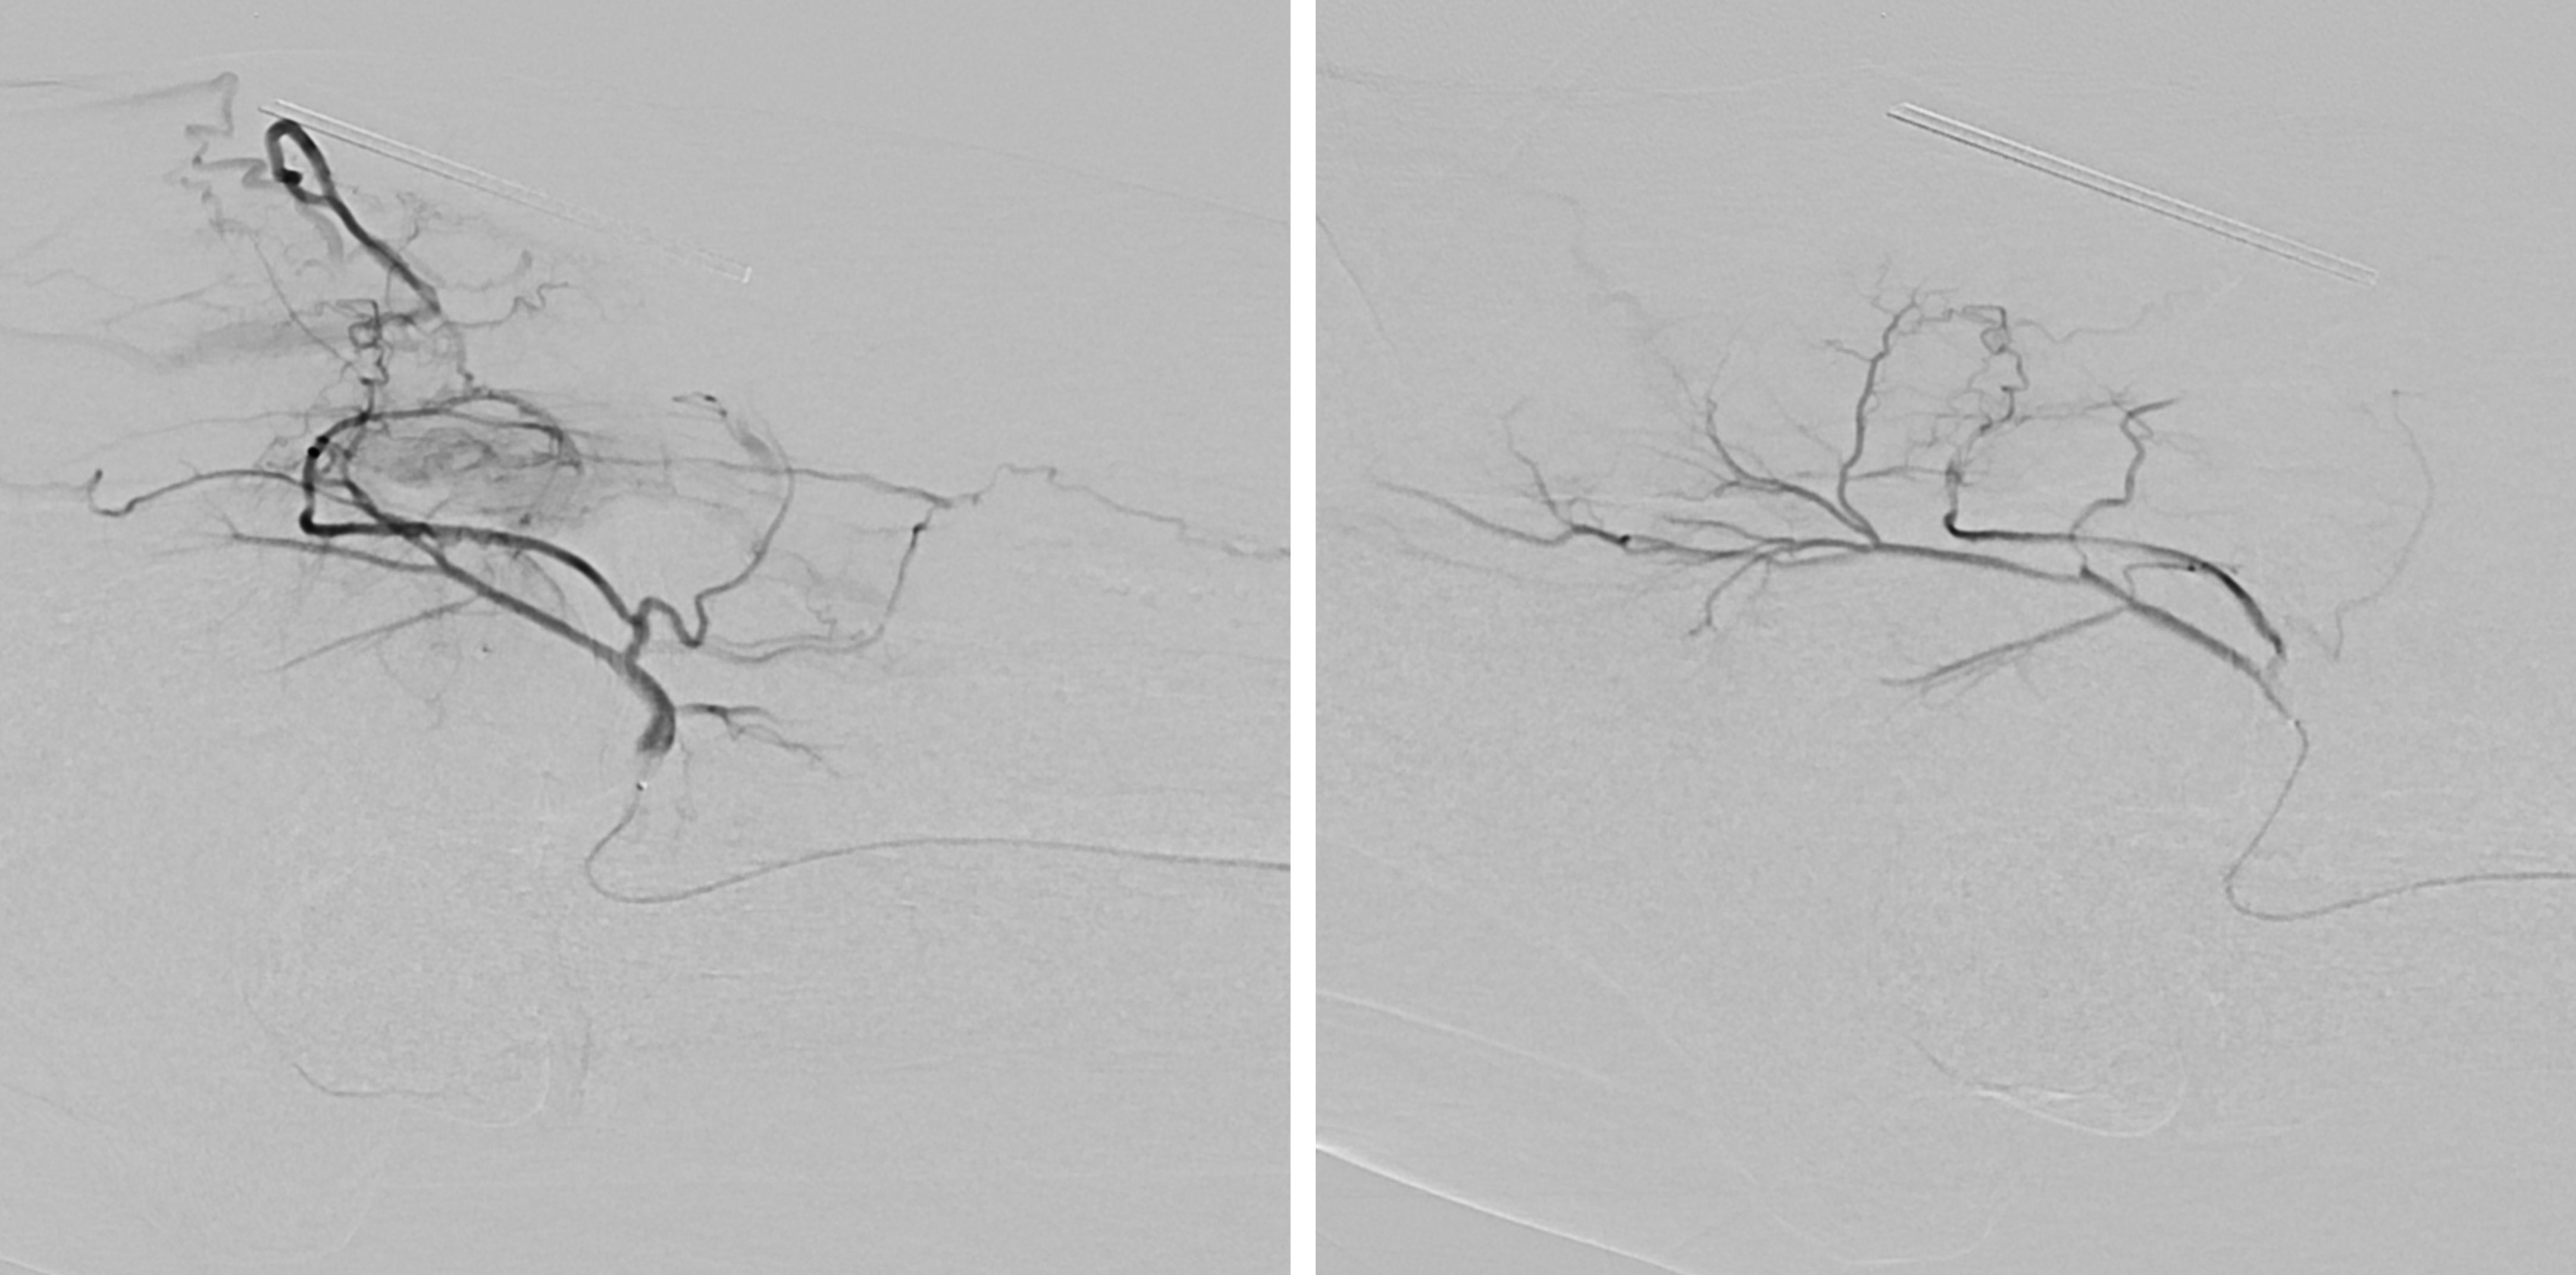

Ist der Tumor für die Embolisation geeignet, und die Leberfunktion gesichert, geschieht der Eingriff an der Abteilung für Kardiovaskuläre und Interventionellen Radiologie. Eine kleine Punktionsstelle in der Leiste reicht, um einen Katheter so einzuführen, dass seine Ende genau vor dem Lebertumor platziert werden kann. Die genaue Platzierung geschieht mit sogenannten Mikrokathetern, welche bis in die kleinsten Gefäße, in sogenannter „superselektiver Technik“, geführt werden können. Dies ist für den Erfolg der Behandlung besonders wichtig. Dann werden von dieser „Abschußrampe“ kleinste Kugeln, sogenannte Partikel, in einer Größe von 300–900μ in die zum Tumor führenden arteriellen Gefäße eingeschwemmt, bis sie diese völlig blockieren und ausfüllen. Danach wird ein geringe Menge „Glubran“, ein Gewebeklebstoff eingebracht, der bewirken soll, daß die Verstopfung der Tumorgefäße auch erhalten bleibt. Mittels moderner angiographischer Techniken kann der Erfolg der Behandlung sofort kontrolliert und bewertet werden. Falls mehrere arterielle Äste zum Tumor führen, können diese alle einzeln, superselektiv, mit den Mikrokathetern erfasst und behandelt werden.

Abbildung 1: Übersichtsangiographie der Leber und superselektive Lage des Mikrokatheters vor Embolisation.

Abbildung 2: Angiographiekontrolle nach Embolisation. Die Tumor versorgenden Gefäße sind verschlossen.

Abbildung 3: Lebertumor vor und nach Embolisation.